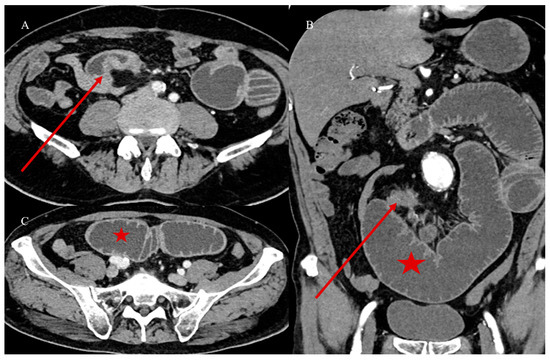

- Marsicovetere, P.; Ivatury, S.J.; White, B.; Holubar, S.D. Intestinal intussusception: Etiology, diagnosis, and treatment. Clin. Colon. Rectal Surg. 2017, 30, 30–39. [Google Scholar] [CrossRef] [PubMed]

- Kim, Y.H.; Blake, M.A.; Harisinghani, M.G.; Archer-Arroyo, K.; Hahn, P.F.; Pitman, M.B.; Mueller, P.R. Adult intestinal intussusception: CT appearances and identification of a causative lead point. Radiographics 2006, 26, 733–744. [Google Scholar] [CrossRef]

- Choi, S.H.; Han, J.K.; Kim, S.H.; Lee, J.M.; Lee, K.H. Intussusception in adults: From stomach to rectum. AJR Am. J. Roentgenol. 2004, 183, 691–698. [Google Scholar] [CrossRef]

- Panzera, F.; Di Venere, B.; Rizzi, M.; Biscaglia, A.; Praticò, C.A.; Nasti, G.; Mardighian, A.; Nunes, T.F.; Inchingolo, R. Bowel intussusception in adult: Prevalence, diagnostic tools and therapy. World J. Methodol. 2021, 11, 81. [Google Scholar] [CrossRef] [PubMed]